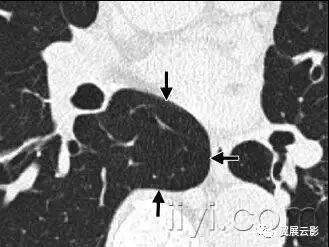

三十、间质性肺气肿

病理:间质性肺气肿的特征是气体位于肺间质之内,尤其是在支气管血管束鞘内,小叶间裂内和脏层胸膜内。最常见于机械通气的新生儿。

平片和CT:成人胸片少见间质性肺气肿,在CT扫描上偶尔可以见到。表现为血管周围透亮影或者低密度晕征和小囊肿。